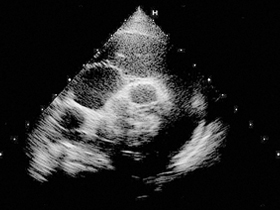

心エコー図検査はBモード(断層像)とDモード(ドプラ法)を駆使して心疾患の多くの情報を得ることができます。心疾患の診断に必要不可欠であり、心不全の診断や治療効果の判定はもちろん、特に心不全に近い状態を判断することができ、臨床徴候が出る前にそのことが分かれば心不全にならないように対処することが可能となります。心エコー図検査はとても有用な循環器検査ではありますが、問題は検者の力量にその診断精度が左右されることでしょう。心エコー図検査は知識と経験が必要であり、そのノウハウを成書から得ることは難しいのです。 このセミナーでは臨床で特に多い4つの病態を取り上げ、それぞれに応じた心エコーの見方、重症度評価、治療への応用などを学び、読み取り方のレベルアップを図ります。 ※※ ご注意 ※※ 当セミナーは「実習セミナー」ではありません。 講義形式となりますので予めご了承の上お申し込み下さい。 ------------------------------------- 第1回 2015年11月18日(水) 「弁膜症」 僧帽弁閉鎖不全症の病態 心エコーでの診断方法(僧帽弁逸脱/腱索断裂/僧帽弁逆流) 重症度による左室流入血流速波形 僧帽弁逆流速波形の変化 僧帽弁閉鎖不全症の治療 第2回 2015年12月16日(水) 「心筋症」 心筋症の定義と分類 心筋症の病態 心エコーでの診断方法(心形態の評価) 左室拡張障害の診断(左室流入血流速波形と肺静脈血流速波形) 心筋症の治療 第3回 2016年01月20日(水) 「先天性心疾患」 短絡疾患(動脈管開存症/心室中隔欠損症/心房中隔欠損症) 狭窄疾患(大動脈狭窄症/肺動脈狭窄症) 複合心奇形などの病態と心エコーでの診断方法 第4回 2016年02月17日(水) 「心膜疾患」 心膜腫瘍、心タンポナーデ、収縮性心膜炎などの病態と心エコーでの診断方法 第5回 2016年03月16日(水) 「症例検討会」